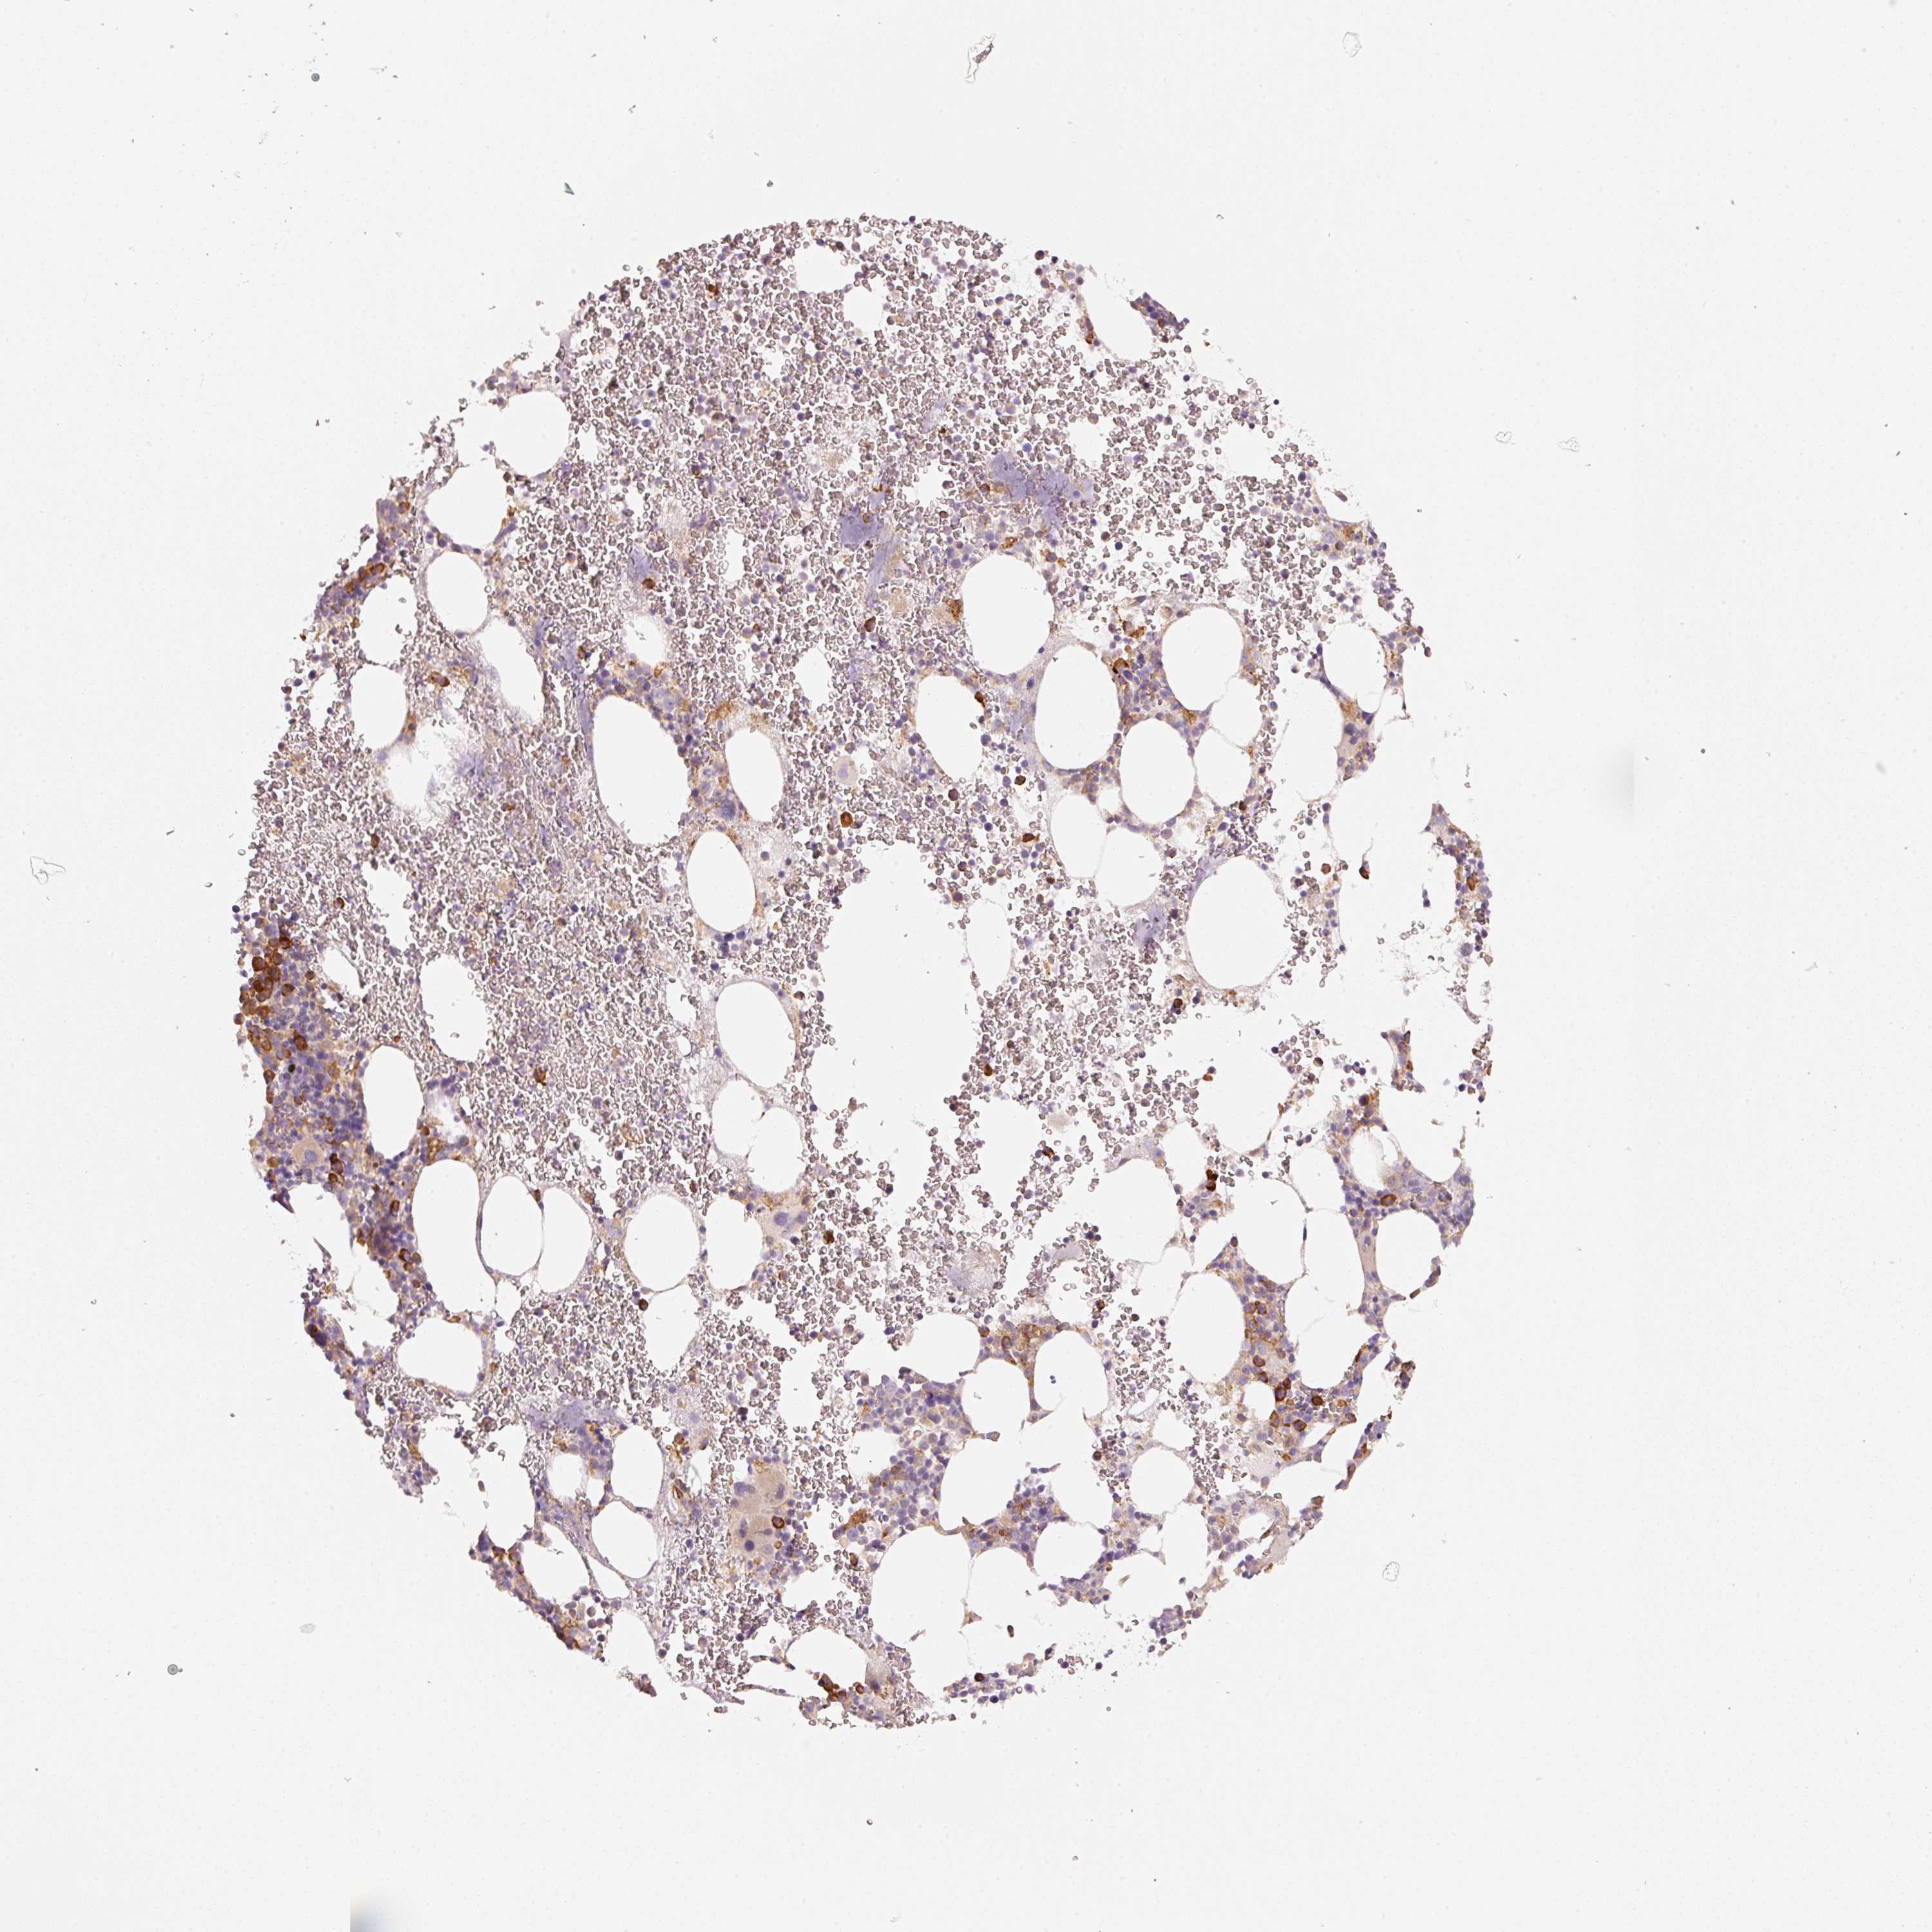

OR13C3